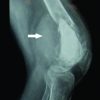

Imaging studies

X-ray images showed a decrease in the intervertebral space of L4/5 and L5/S. On the other side, in the intervertebral space of L3/4, maintaining the intervertebral disc heights, and instability was unclear (Fig. 1). MRI of the lumbar spine revealed a rounded lesion (size, 10 mm × 12 mm × 10 mm) from the right L3/4 facet joint that appeared hypointense on T1- and T2-weighted MRI (Fig. 2a and b). The lesion occupied the right side of the spinal canal to the right intervertebral foramen of L3/4, and exclusion of L3 and L4 nerve roots was observed. By CT imaging, the lesion was well delineated to be completely calcified (Fig. 2c and d).